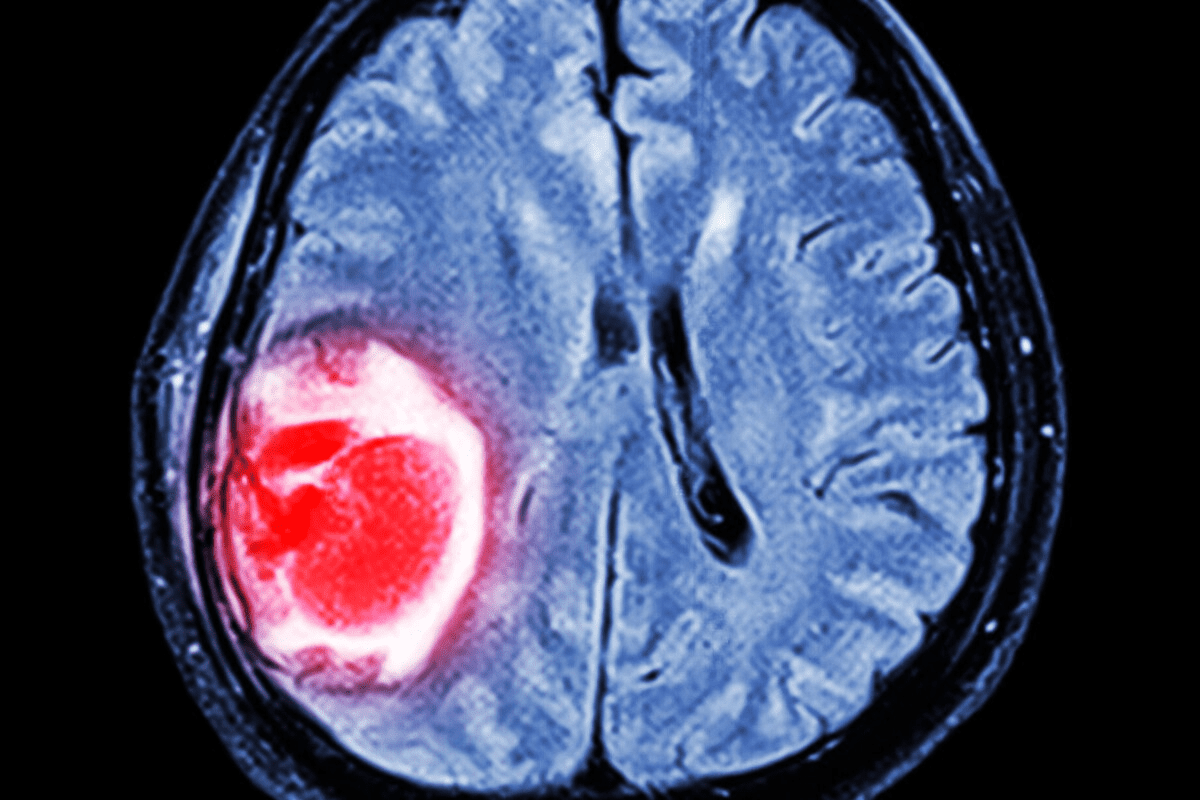

Color Mapping and Brain Activity

Color mapping is key in SPECT scan interpretation. Different colors show different brain activity levels. Hotter colors mean higher activity, and cooler colors mean lower activity.

This method lets psychiatrists spot patterns and anomalies in brain activity. It helps in making a more accurate diagnosis.